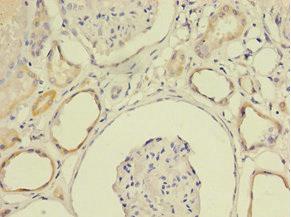

ApplicationELISA, IHC, IF; Recommended dilution: IHC:1:20-1:200, IF:1:50-1:200